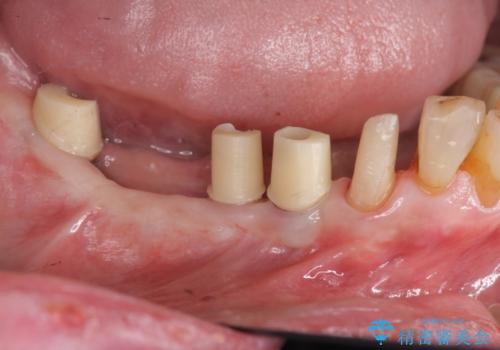

- 奥歯を失い噛めない、しっかりと噛めるようになりたいと希望され来院されました。

清掃性に優れたジルコニアカスタムアバットメント、ジルコニアクラウンを用いて機能性だけでなく審美性・予知性を高めます。

- 130万円(HAインプラント×3・骨造成・ジルコニアカスタムアバットメント×3・ジルコニアクラウン×4)費用は治療当時の料金となります